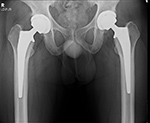

Total Hip Replacement

Total hip arthroplasty (THA) is the most common total hip replacement. It uses two components, a stemmed femoral component with a prosthetic femoral head and a prosthetic acetabular component (figure: modular total hip arthroplasty; figure: bilateral total hip arthroplasty). In 2011 there were 306,000 total hip replacements which is only second to 645,062 total knee replacements (AAOS). There were also estimated to be 105,509 partial hip replacements.

For patients younger than 65 with a normal life expectancy and adequate bone mass, cementless femoral stems are preferred (figure: bilateral total hip arthroplasty in 38 year-old man). It is possible that a femoral stem which has become well ingrown will not require revision, even if the acetabular component, and the articulating femoral head may need revision in the future. However, as in most cases with orthopedic surgery, the choice of components and the use of cemented or cementless femoral component depends on the surgeon's preference and experience. With any type of joint replacement, there is concern for its longevity and the need for ultimate revision or complete replacement. Revision surgery is usually not easy and may not have good results. Therefore, joint replacement is avoided as much as possible in younger patients and put off as long as is reasonable.

Bilateral total hip arthroplasty (THA) |

38 year old man with bilateral THA for advanced osteoarthritis. |

| Bilateral total hip arthroplasty (THA) |

| 38 year old man with bilateral THA for advanced osteoarthritis. The acetabular cup on an AP view of the pelvis should have 30-50 degrees of lateral inclination, which is measured as the angle between the rim of the acetabular cup and a line tangential to the ischial tuberosities. |

38 year old man with bilateral THA for advanced osteoarthritis. On a true cross-table lateral view of the hip there is normally 5-25 degrees of anteversion which is measured as the angle between the rim of the acetabular cup and a line drawn perpendicular to the horizontal surface. |

38 year old man with bilateral THA for advanced osteoarthritis. The distances from a line (C) between the centers of the femoral heads to a line running tangential to the ischial tuberosities (A) should be equal on each side, and the distances between the centers of the femoral heads to a line (B) running tangential to the tops of the greater trochanters should be equal on each side. Lines A, B, C should be parallel. |

38 year old man with bilateral THA for advanced osteoarthritis. The distances from the centers of the femoral heads on each side to the tops of the acetabular tear drops should be equal. |